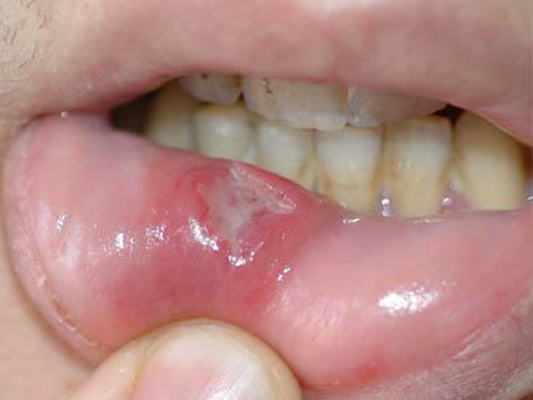

口腔癌圖片

口腔癌的前兆 (6)

口腔癌的前兆 (7)

口腔癌的前兆 (8)

口腔癌的前兆 (9)